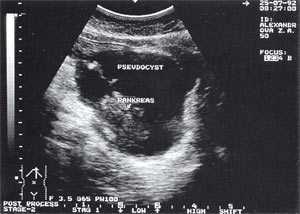

Оментобурсит (рис. 3) встречается в 28,4% случаев (из них 48% у мужчин и 52% у женщин). Некоторые авторы обозначают эту патологию как "псевдокиста поджелудочной железы". Отмечен объем таких образований от 5мл (малые объемы необходимо дифференцировать с сосудистыми аневризмами) до 3 л и более. Скорость формирования оментобурсита при остром панкреатите от 2 - 4 дн. от начала заболевания до 2 - 4 нед. При ультразвуковом исследовании оментобурсит представлен в виде анэхогенного образования с четкими контурами, неправильной или округлой формы, чаще с однородной структурой, с толщиной стенок 0,2 - 0,4 см. При эхографическом мониторинге утолщение стенки до 0,5 - 1,0 см с появлением неоднородности структуры следует расценивать как сонографический признак абсцедирования.

Рис. 3. Псевдокиста поджелудочной железы при остром панкреатите в виде анэхогенного образования с четкими контурами, однородной структурой, с наличием гиперэхогенных включений (детрит поджелудочной железы).